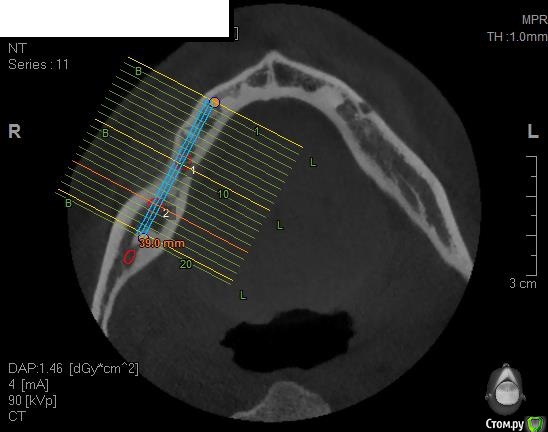

Павел7809 Опубликовано 21 ноября, 2017 Поделиться Опубликовано 21 ноября, 2017 Здравствуйте коллеги! Собственно ситуация на скринах. Для сосиджа как то экстремально большой объем. Блоки? Сетка?(ох как не хочется! последняя развалилась....) Крыша гаража? Из инструментария есть абсолютно все... Ссылка на комментарий

Павел7809 Опубликовано 21 ноября, 2017 Автор Поделиться Опубликовано 21 ноября, 2017 Коротышки с десной не рассматриваете? с удалением 8киинтересная идея...в принципе 2 астры туда влезают 4 на 6, боюсь просто эстетически получится некрасиво Ссылка на комментарий

Павел7809 Опубликовано 21 ноября, 2017 Автор Поделиться Опубликовано 21 ноября, 2017 Платформы имплантов будут на уровне апексов соседних зубов. Это будет эстетический ад. Ссылка на комментарий

Павел7809 Опубликовано 22 ноября, 2017 Автор Поделиться Опубликовано 22 ноября, 2017 (изменено) Да, но проблема в том , что на место 7 ки как бы и 6мм не влезает. Вообще мысль появилась поставить короткую 6 ку на месте 6 го зуба, удалить 8, поставить на его место имплант(там с местом проблемы нет, и сделать мостик) . Ну или сетка(ой как не хочется!) Мало того я посмотрел и понял что элементарно влезают восьмерки в обл 36 38 Изменено 22 ноября, 2017 пользователем Павел7809 1 Ссылка на комментарий

Павел7809 Опубликовано 25 ноября, 2017 Автор Поделиться Опубликовано 25 ноября, 2017 Пообщался с пациентом. Сошлись на коротышках 4 на 6 в область 7 ки, 9 на 4 в области 6 4ки. Да и по факту я посмотрел - коронки не будут такими уж огромными выглядеть. 1 Ссылка на комментарий